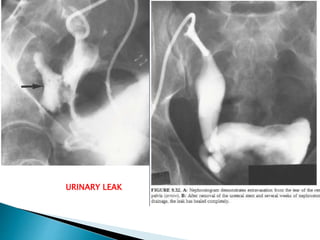

1. Urinary leak

URINARY LEAK